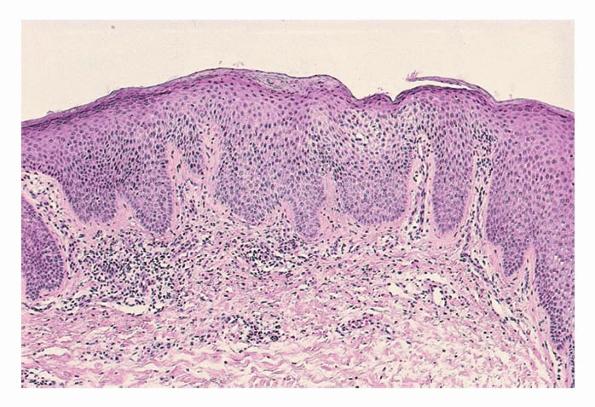

HistopathologyNummular dermatitis is the prototype of subacute spongiotic dermatitis . There is mild to moderate spongiosis, usually without vesiculation. Irregular acanthosis with some exocytosis of inflammatory cells is usually present. The parakeratotic stratum corneum contains aggregates of coagulated plasma, forming a crust. Mild papillary dermal edema and vascular dilatation may be present.

There is superficial perivascular infiltrate of lymphocytes, some eosinophils, occasional neutrophils, and plasma cells.